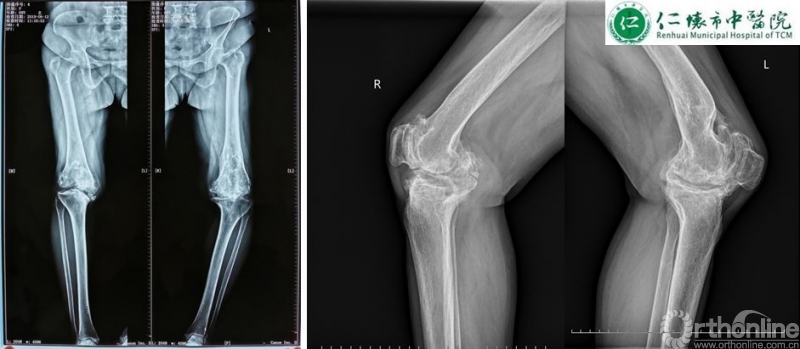

课程分享结束后,进入病例分享环节,四家与会医院分别展示各自病例并就术中存疑和李子剑教授探讨取经。仁怀市中医院分享了一例经典的使用ACCK假体复杂右膝关节置换手术:

术前影像:

术前规划:

李子剑教授对仁怀市中医院这例手术的术前规划方案和假体选择表示充分的肯定,对术后力线及假体位置同样表示赞赏。对于仁怀市中医院各位主任提出的关于未来左膝关节置换的相关问题,李教授给出了使用定制化导板截骨的中肯建议,并分别分析了ACCK,AHK和肿瘤假体在这例病例中应用的可能性及利弊,各位专家集思广益,不断碰撞出学术的火花。